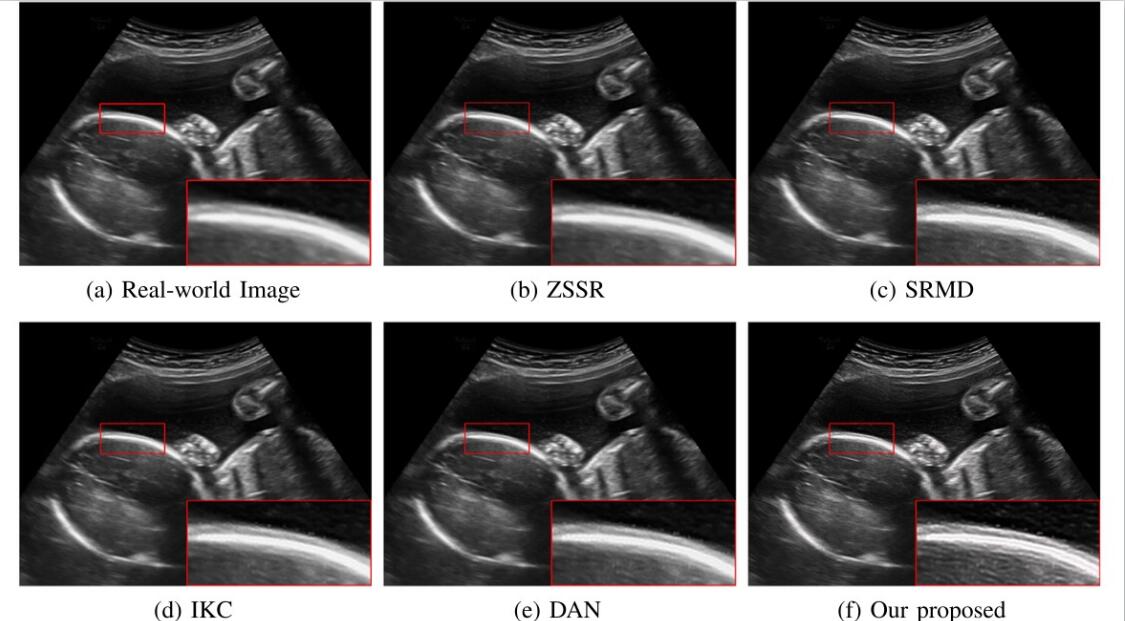

对于超声临床诊断而言,超声影像超分辨(ultrasound image super-resolution)可以提高超声成像质量,从而提高疾病诊断的准确性。但由于传感设备和传输介质的差异,实际场景中超声成像其退化模糊过程是未知且不可控的。为了解决未知退化场景超声医学影像准确超分辨的难题,团队提出了一种有效的基于退化模糊自估计且结合渐进残差学习和记忆提升机制的超声影像盲超分方法,初步实现了真实场景超声影像准确超分辨。相关研究成果发表在人工智能、计算机医学信息交叉领域一区TOP期刊《IEEE Journal of Biomedical and Health Informatics》(IF: 7.7)。今年会为论文第一完成单位,计算机学院刘恒教授、硕士生刘建勇分别为论文第一、第二作者。

(真实场景超声影像盲超分效果对比图)